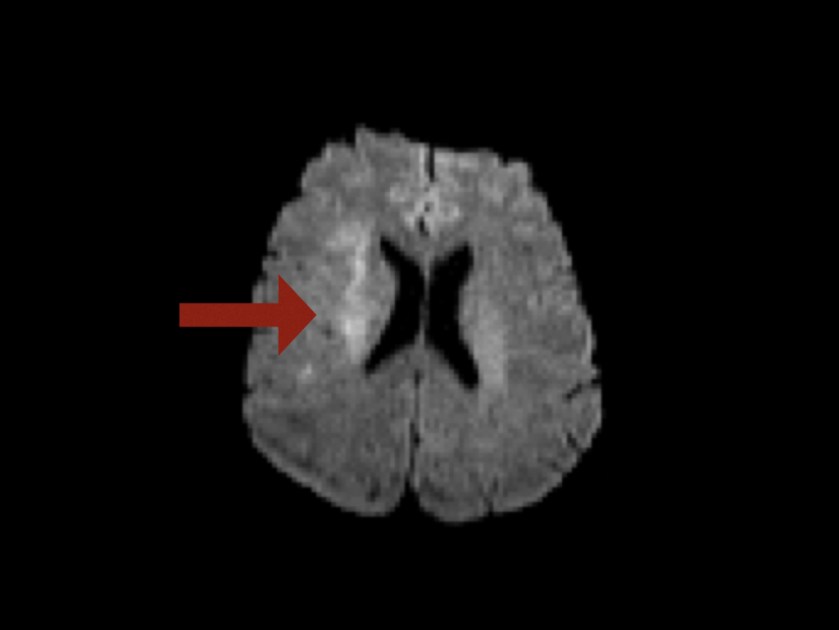

Diffusion:

Im Versorgungsgebiet der rechten A.cerebri media stellt sich ein beginnend diffusionspositives Areal dar (Pfeil).